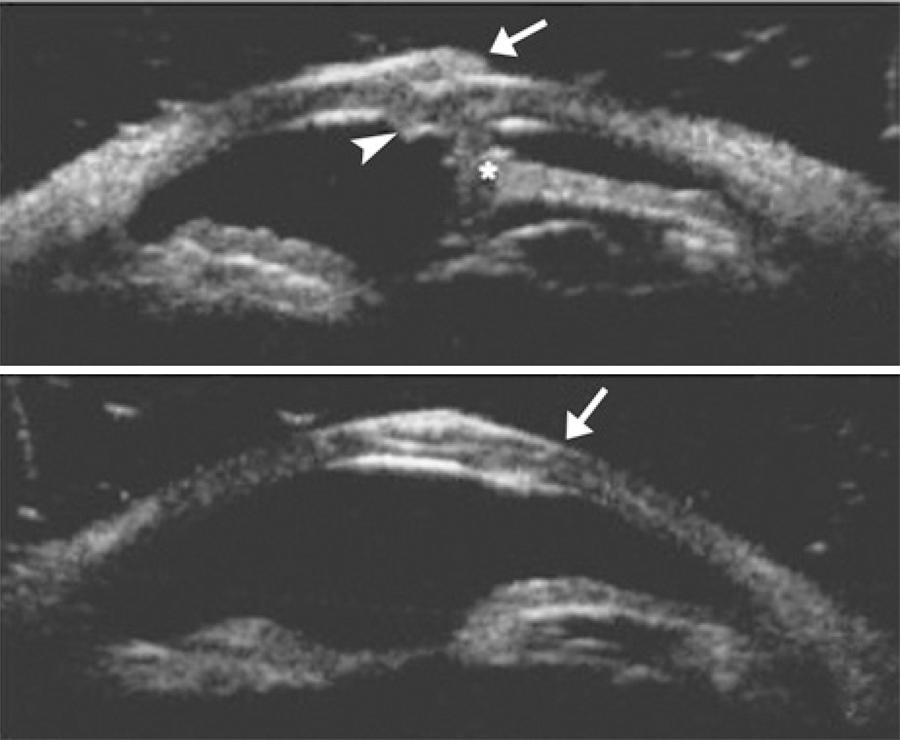

Slit lamp findings were inconclusive; we used UBM to define the wound architecture in detail. UBM was performed with the patient in the supine position after receiving topical anesthesia. A 50-MHz probe was used with an immersion technique (OTI Scan, Ophthalmic Technologies, Inc.). UBM images demonstrated significant overriding of the corneal wound edges in the central part of the cornea (Figure 2 A). We discussed surgical alternatives with the patient and suggested adjustment of the corneal sutures before starting management of the vitreous hemorrhage.

Figure 2 Preoperative ultrasound biomicroscopy of the cornea showing overriding of the wound edges (white arrow demonstrates the upper flap, white arrow head demonstrates the lower flap and asterisks demonstrate the anterior synechia) (A). Postoperative ultrasound biomicroscopy of the cornea showing correct apposition of the wound edges (white arrow indicates the start point of the oblique laceration on the anterior surface of the cornea) (B).

Surgery was performed under general anesthesia. All of the corneal sutures were cut and re-sutured according to the oblique architecture of the wound. The postoperative 6-week visit demonstrated proper alignment of the cornea (Figure 1 B). The structure of the wound edges was analyzed with UBM, demonstrating correct apposition of the corneal wound edges (Figure 2 B). The patient was managed with pars plano vitrectomy, and visual acuity was 20/200 at his last visit at 4 months after the corneal laceration.